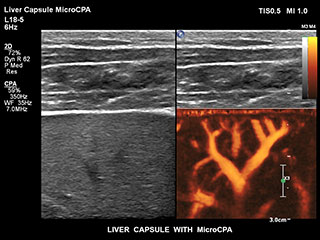

Получение информации о кровотоке в мелких сосудистых структурах с небольшим кровотоком традиционно считается сложной задачей. Благодаря новой функции MicroCPA в системе EPIQ визуализация капиллярного кровообращения с низкой скоростью кровотока выполняется быстро и просто, обеспечивая более точную диагностику при оценке перфузии органов и сети небольших сосудов.